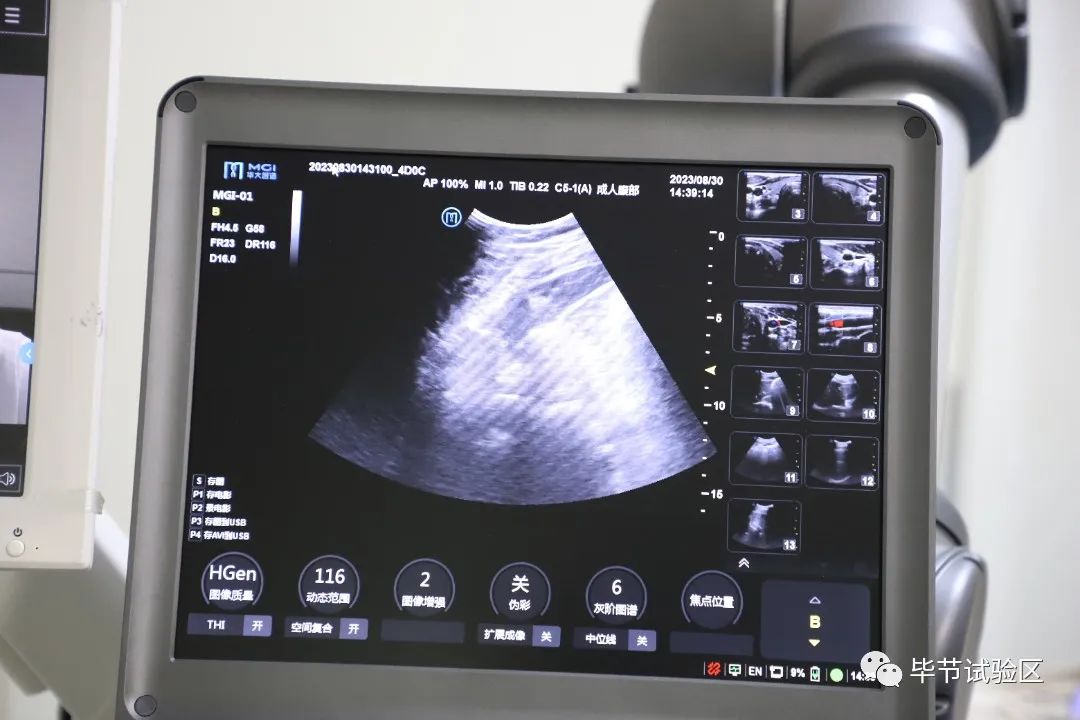

2023年8月30日,華大智造5G遠(yuǎn)程超聲機(jī)器人MGIUS-R3在浙江省人民醫(yī)院畢節(jié)醫(yī)院投入使用。

遠(yuǎn)程超聲檢測(cè)室內(nèi),浙江省人民醫(yī)院超聲醫(yī)學(xué)科副主任醫(yī)師葉瑞忠在輔助醫(yī)務(wù)人員的輔助下,實(shí)時(shí)視頻操控遠(yuǎn)程超控機(jī)械臂分別為兩位患者做了甲狀腺、頸動(dòng)脈超聲檢查及肝、膽、胰、脾、腎超聲檢查,并現(xiàn)場(chǎng)出具診斷書。

該設(shè)備是已通過國(guó)家藥品監(jiān)督管理局三類醫(yī)療器械認(rèn)證的超聲機(jī)器人診斷系統(tǒng),在5G、4G、WIFI或者寬帶網(wǎng)絡(luò)連接下,醫(yī)生可異地通過醫(yī)生端的仿形探頭遠(yuǎn)程操作病人端機(jī)械臂進(jìn)行超聲掃查,并遠(yuǎn)程調(diào)節(jié)病人端超聲參數(shù),實(shí)現(xiàn)遠(yuǎn)程診斷。